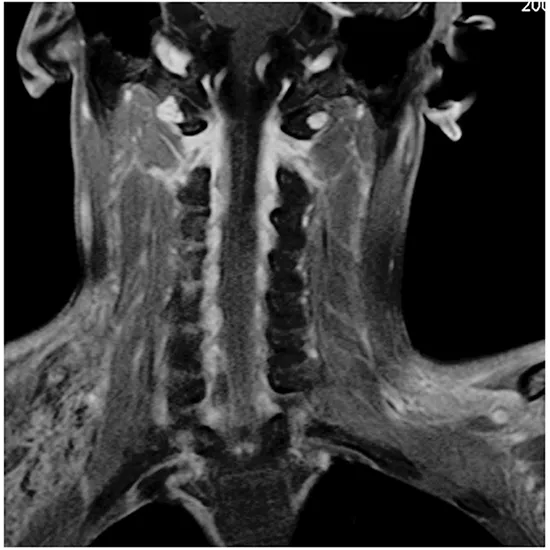

MRI Cervical Spine C Brachial Plexus is an imaging procedure used to assess the anatomy and pathology of the brachial plexus, which is the region on each side of the neck where nerve roots from the spinal cord split into nerves of each arm. It is also known as MRI CX Spine C Branchial Plexus.

The brachial plexus emerges from cervical spinal nerves i.e C5 to C8 and the first thoracic spine T1.